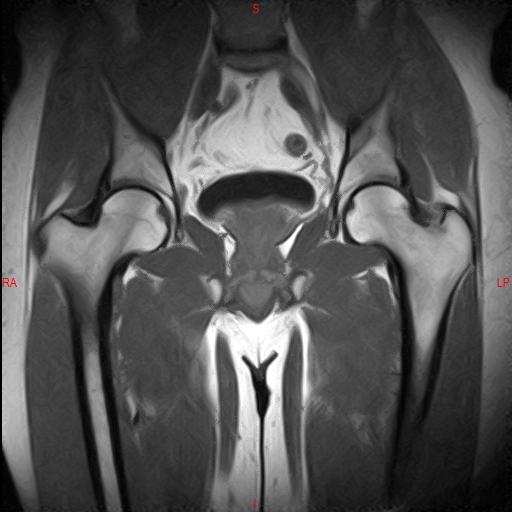

• RESONANCIA NORMAL CADERAS T2 CORONAL

• RESONANCIA NORMAL CADERAS T1 CORONAL